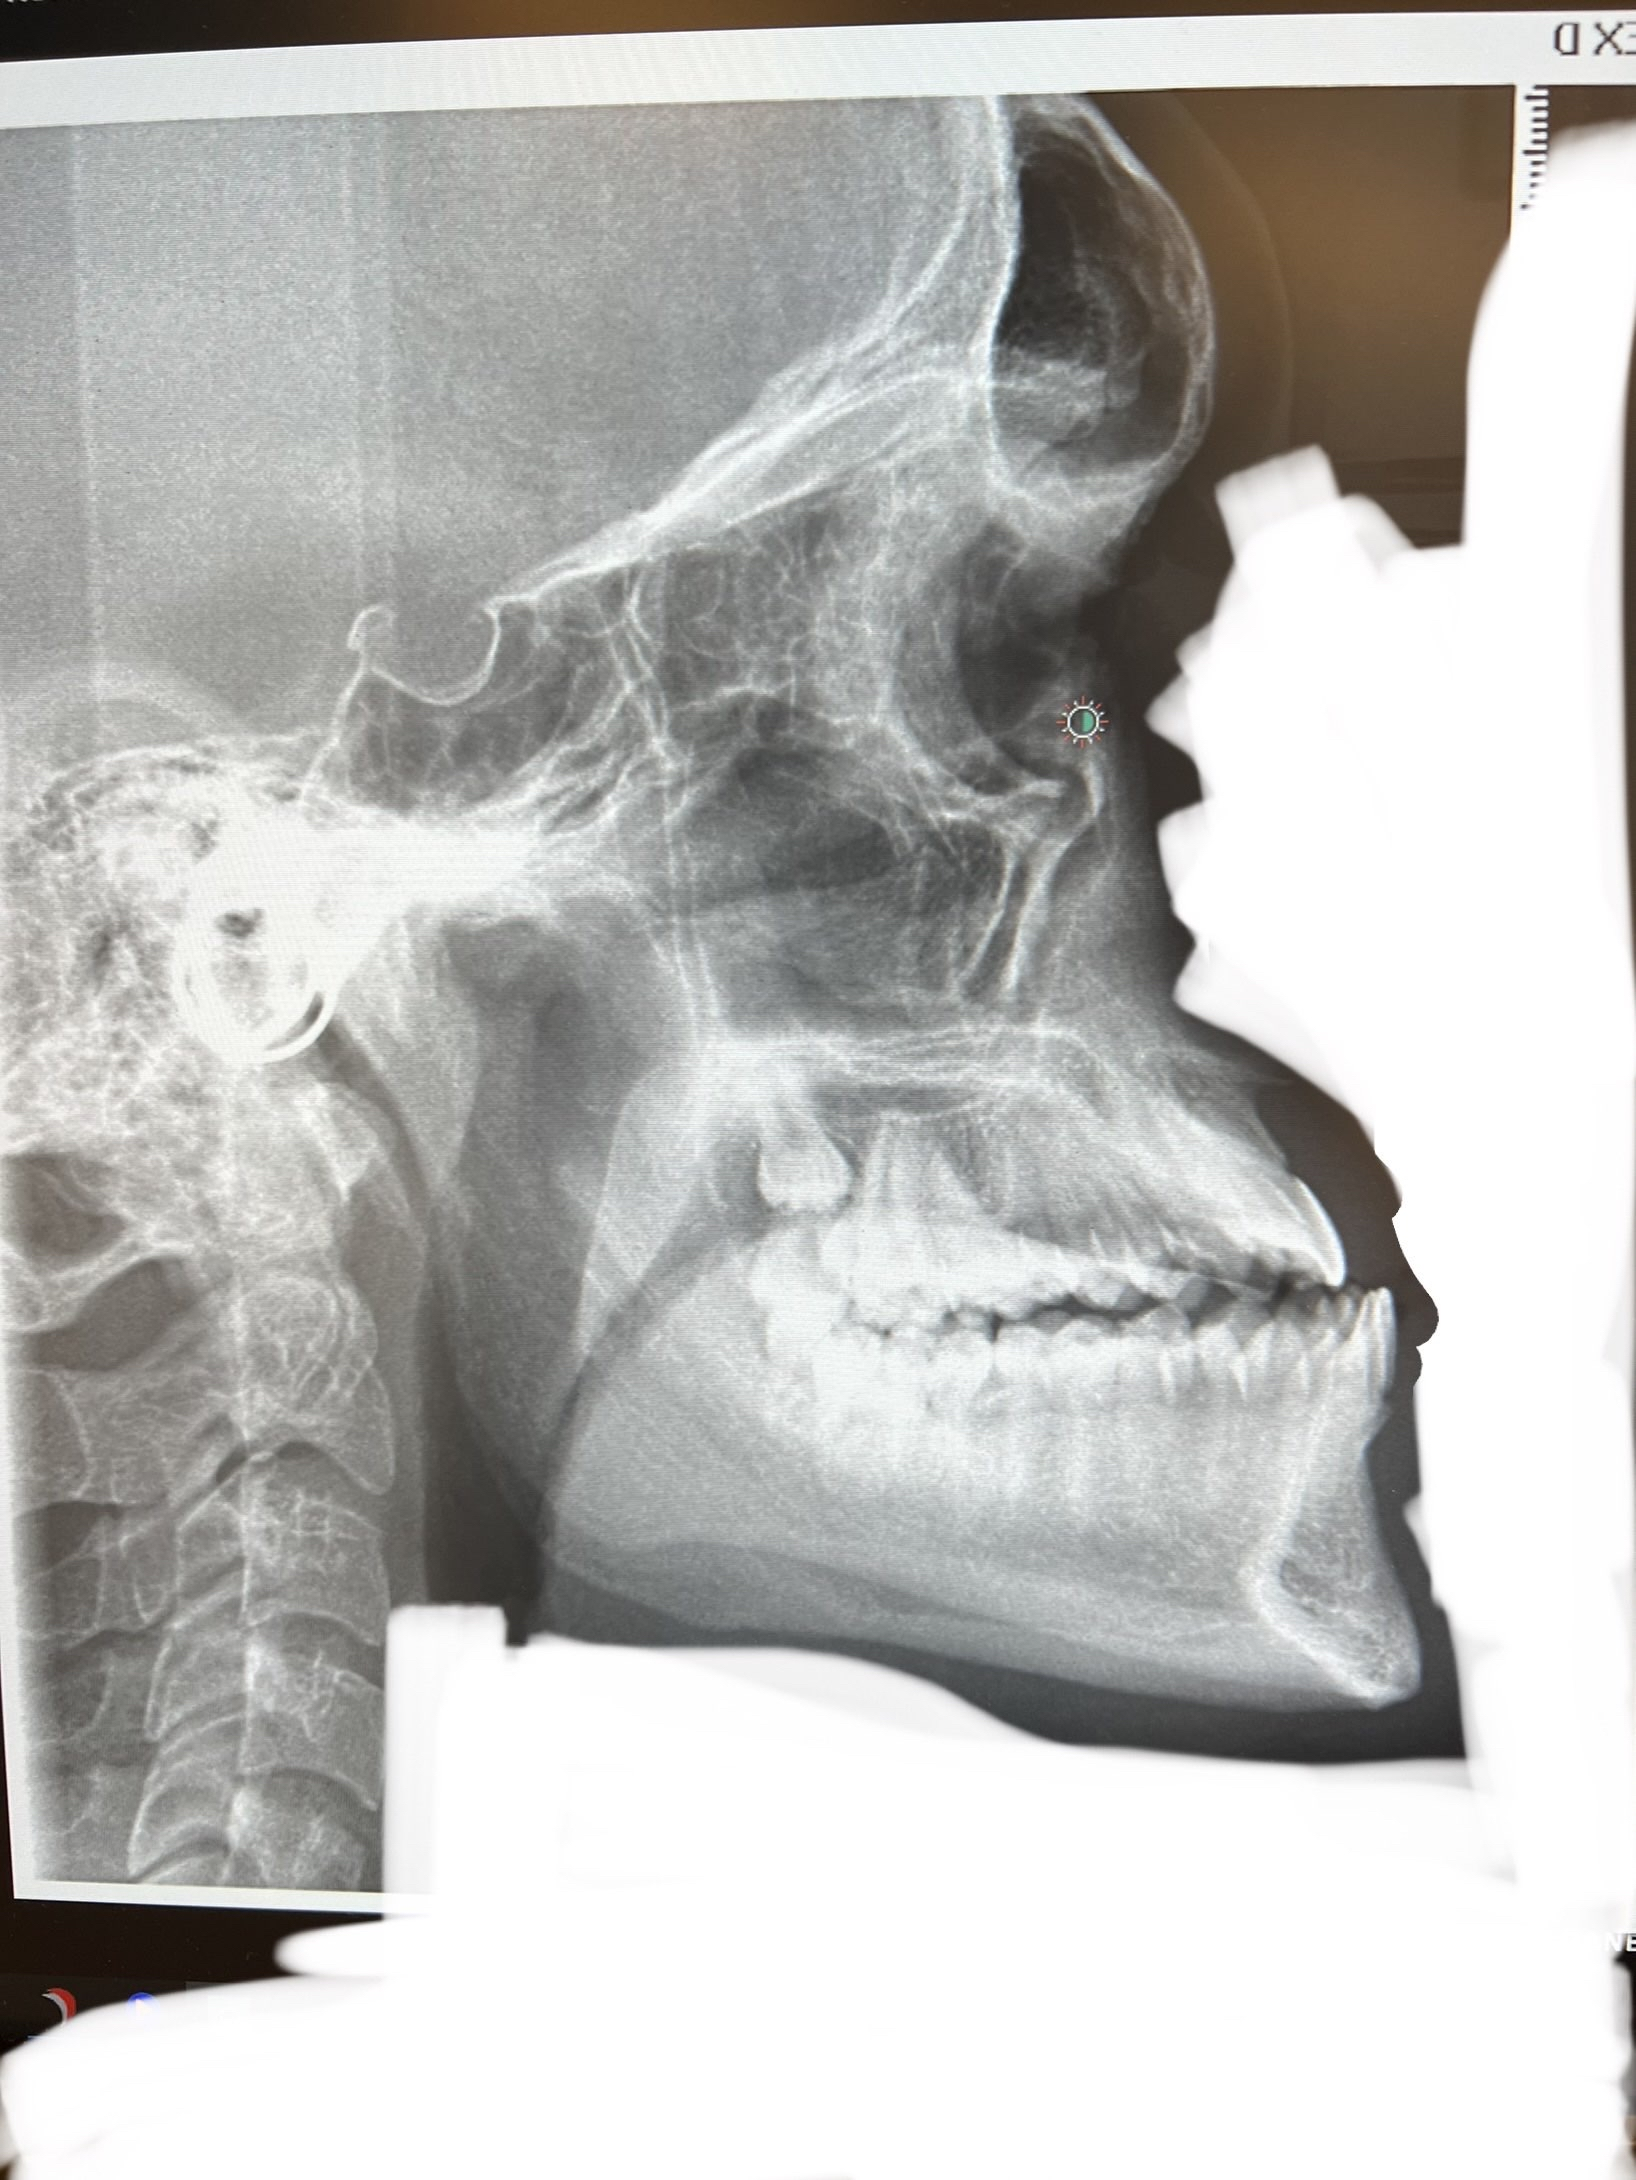

This person with a textbook class 3 and an exceptionally wide airway (probably around 3 times larger than average), could undergo DJS with significant maxillary movement and end up mogging while still preserving their airway size.